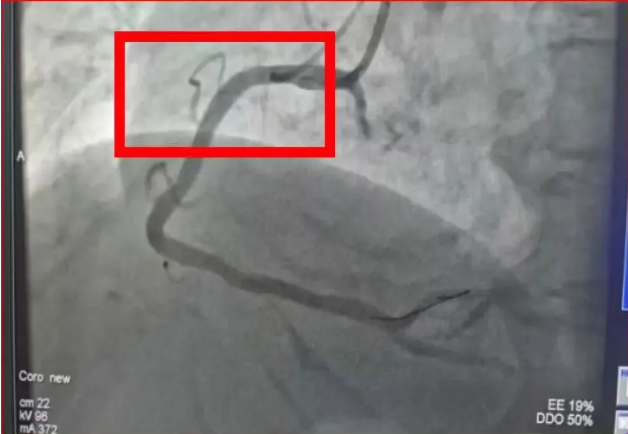

09:48,救护车呼啸着冲进宜宾市第五人民医院医共体总院大门,早已等候的医护人员立即给予口服心梗一包药;10:01复查心电图显示明显动态演变;10:09患者进入导管室;10:14,造影显示右冠状动脉近段完全闭塞,与心电图诊断完全一致。心内科团队随即熟练地植入一枚支架,开通血管。